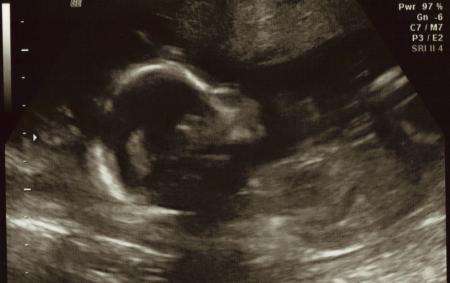

und von heute vom organ screening zuerst der größere mit 21 cm un 300g

Bild zu